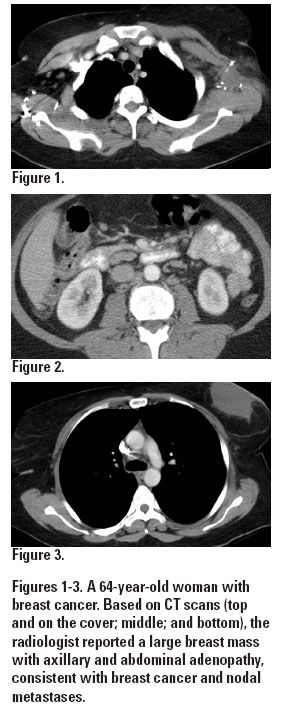

Dr. Coakley illustrated the importance of providing a complete clinical history to the radiologist with the case of a 64-year-old woman with breast cancer. On the basis of imaging studies, the report came back as a large breast mass with axillary and abdominal adenopathy, consistent with breast cancer and nodal metastases (see Figures 1-3).

“On the face of it, that interpretation was justifiable, until you get the extra information: she was two months’ postsurgery so the breast and axillary changes were likely postoperative,” he said. “She had a negative PET for those nodes in the abdomen (see Figure 4). She had hepatitis C and we often see reactive nodes in that setting, so probably those abdominal nodes were reactive and not metastatic. All that missing information totally changes the interpretation.”